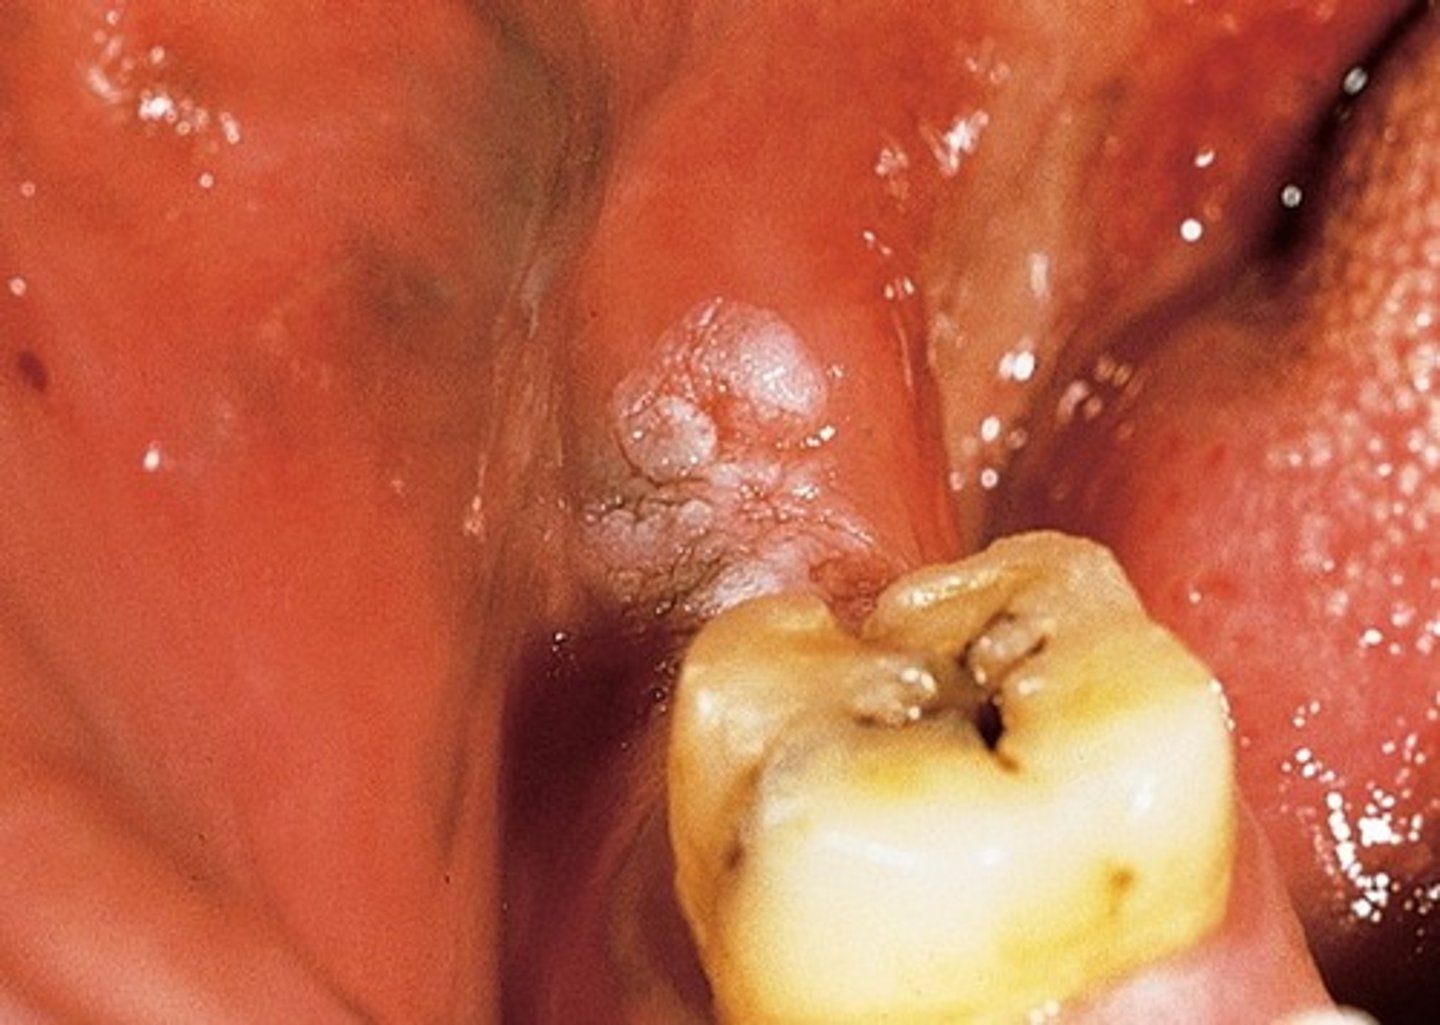

What is verrucous carcinoma? (+ location, population, assoc. with)

diffuse white (or mixed) pebbly plaque

⢠common location: vestibule

⢠population: males over 65

⢠associated with smokeless tobacco

⢠slow growth